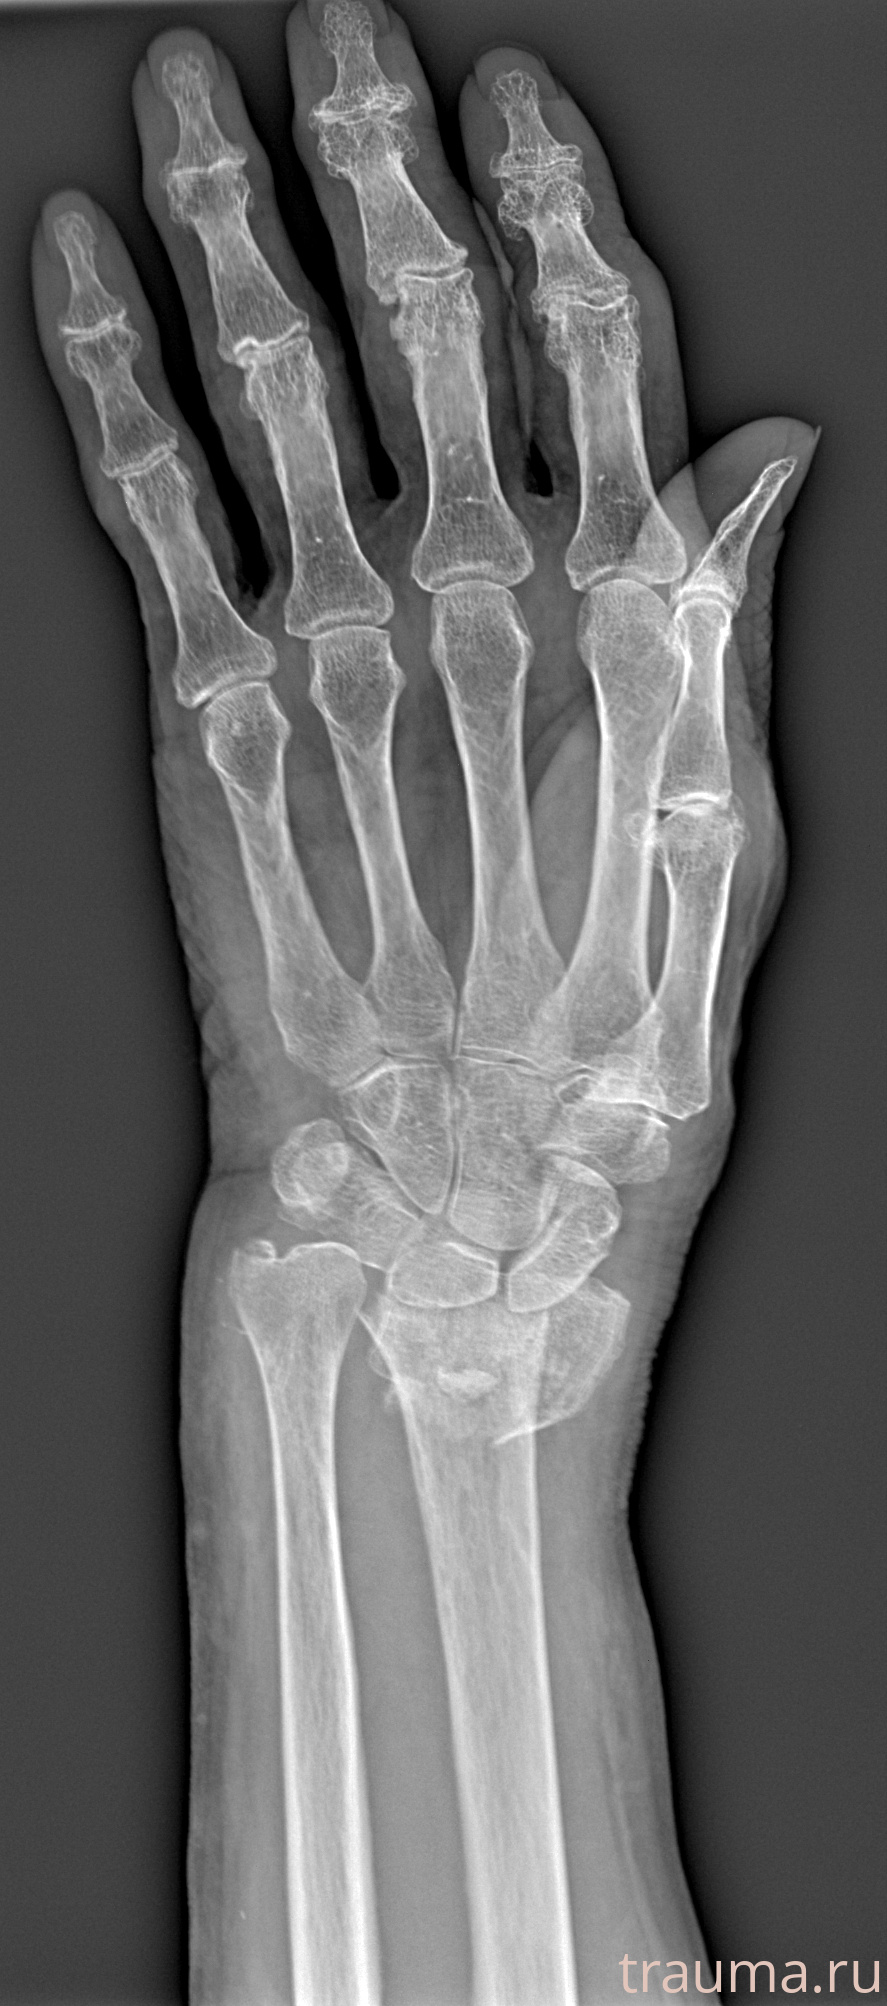

Рентгенограммы

Рентген на дому: по вашему адресу приезжает врач-рентгенолог, травматолог-ортопед с мобильным рентгеновским аппаратом, проводит диагностику травмы или заболевания, делает необходимые рентгенограммы, дает рекомендации по дальнейшему лечению. Получить качественные снимки в домашних условиях возможно благодаря уникальной методике, разработанной МосРентген Центром для института  Склифосовского